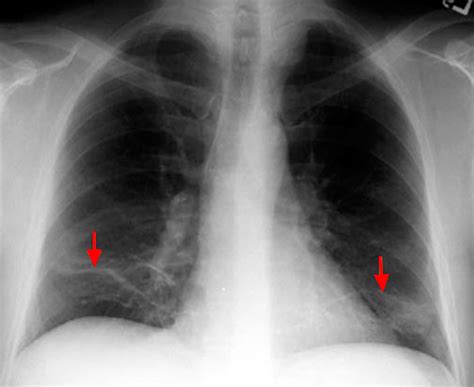

linear atelectasis in both lung bases